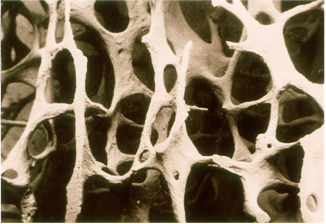

正常骨骼:结构紧密,如同质密的蜂窝,孔隙小且均匀,支撑力强。

疏松骨骼:骨量流失,孔隙变大、结构稀疏,骨骼变脆,易导致骨折。